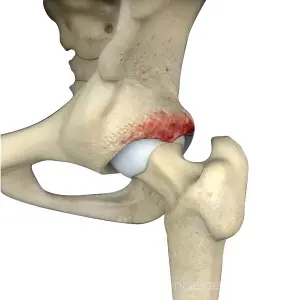

Hip Deformity

Hip deformities can be debilitating, affecting ...